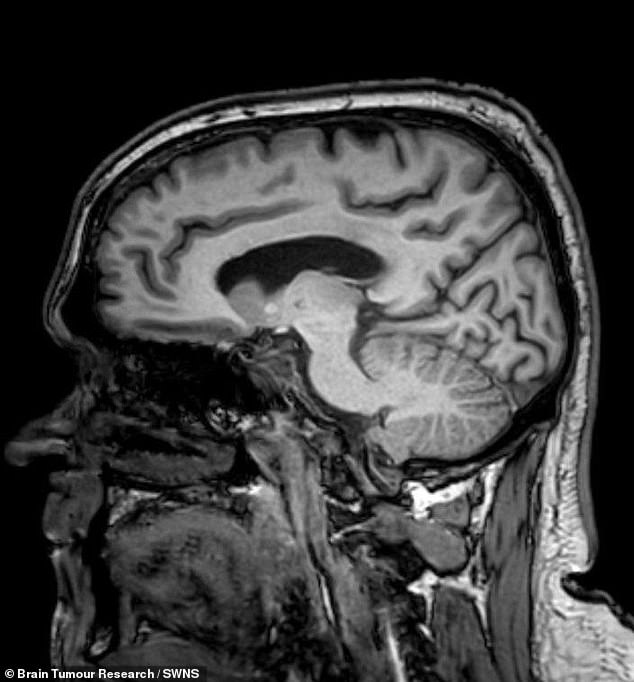

At Chesterfield Royal Hospital, scans revealed the shocking truth: Brunt had a glioblastoma, a highly aggressive and incurable form of brain cancer. Doctors initially expected to find evidence of a bleed from the crash, but instead, they uncovered a tumour that required urgent intervention. He was referred to Royal Hallamshire Hospital in Sheffield, where surgeons performed a craniotomy to remove the visible tumour. The procedure left Brunt relearning basic functions like walking and speaking, but with determination, he endured the grueling recovery.